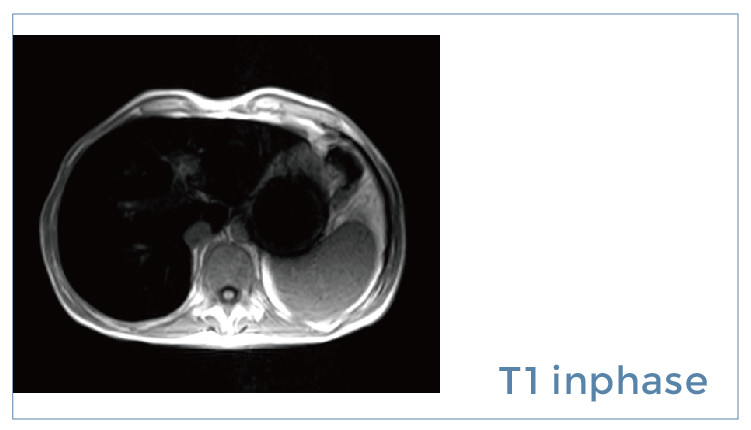

【朗润影像档案】磁共振影像病例分享(编号20190914)